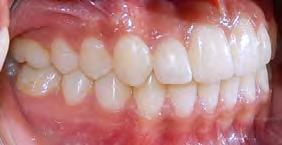

Caso clínico

Se presenta una paciente de 13 años 5 meses con el motivo de consulta “es que no me baja el colmillo”. En los estudios extraorales se ve el perfil concavo y labios en contacto durante el reposo (Figura 1). En los estudios intraorales tenemos , clase I esquelética, con crecimiento hipodivergente (Figura 2), clase II molar derecha y clase I molar y canina izquierda, la clase canina derecha no determinada

Figura 1. Perfil, frente en reposo, sonrisa.

(ND), órgano dental (OD) 13 retenido, mordida abierta en sectores laterales, overjet de 3 mm y overbite de 10%, líneas medias dentales desviadas y microdoncia de OD 12 y 22.